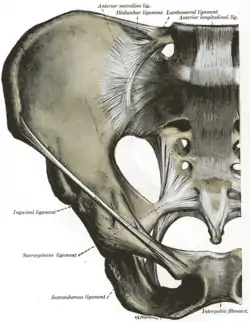

Articulations of pelvis. Anterior view.

Articulations of pelvis. Anterior view. Articulations of pelvis. Posterior view.